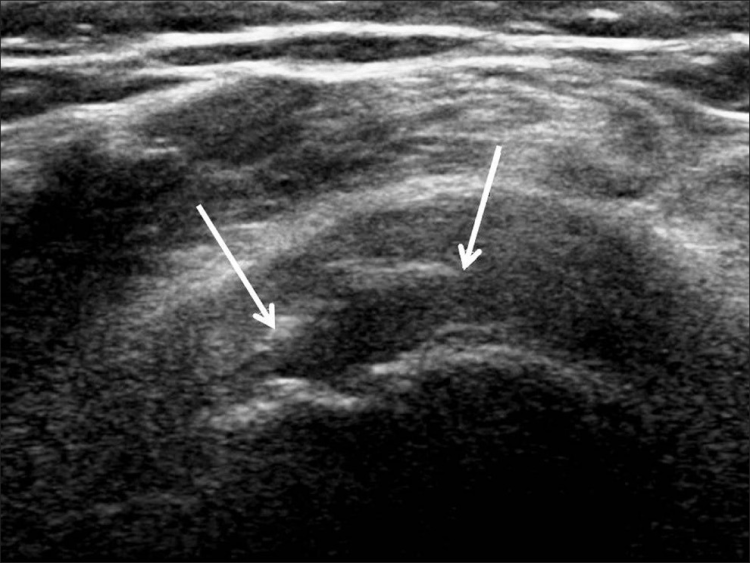

Los desgarros del manguito de los rotadores son la patología más común que se encuentra en los exámenes de ultrasonido del hombro.[7] La incidencia de lágrimas aumenta con la edad. Los desgarros de tendones se pueden clasificar de acuerdo con el grado de falla de la fibra, que van desde desgarros completos [Figura 7], desgarros de espesor total [Figuras 8, 9], desgarros de espesor parcial [Figuras 10-12] y desgarros intrasustancia [Figura 13 ]. Un desgarro agudo suele ir acompañado de derrame articular o bursal [Figura 12]. [7-9] La ausencia de derrame generalmente se relaciona con desgarros crónicos.[9] En un metanálisis sobre la precisión de la resonancia magnética, la artrografía por resonancia magnética y la ecografía en el diagnóstico de desgarros del manguito de los rotadores, la ecografía ofreció una alta sensibilidad y especificidad para la evaluación de los desgarros del manguito de los rotadores de espesor total (92,3 y 94,4 %, respectivamente) con 85,1 % y 92 %, respectivamente para todas las lágrimas.[7] El desgarro de espesor parcial aparece como un defecto o hendidura hipoecogénica en el tendón, afectando solo una parte de su espesor, mientras que un desgarro de espesor total se extiende desde la bolsa hasta la superficie articular del tendón. Un desgarro completo es un desgarro de espesor completo que afecta todo el ancho del tendón. El tendón se retrae medialmente, y la cantidad de retracción depende de la edad del desgarro. En las roturas crónicas, el tendón desaparece por debajo del arco coracoacromial, dejando la cabeza humeral descubierta por el supraespinoso, el denominado signo de la "cabeza desnuda". Los hallazgos de la ecografía incluyen la falta de visualización del tendón y la hernia del músculo deltoides. Los desgarros intrasustancia permanecen localizados en el tendón sin afectar sus márgenes. Los desgarros intrasustancia y de espesor parcial pueden ser difíciles de diferenciar de la tendinopatía focal.